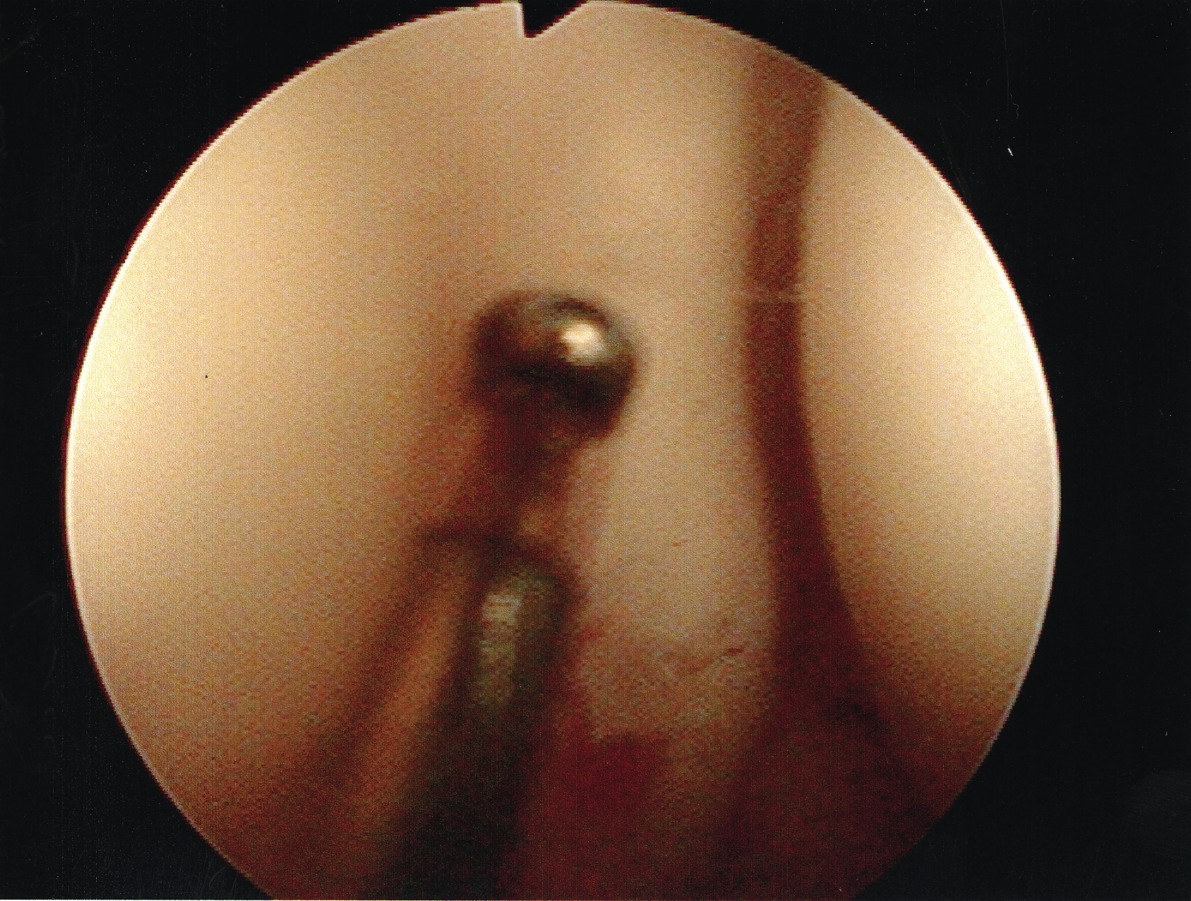

Accordingly, we recently undertook a study to evaluate the technical ease of using this approach to treat patients with plantar plate derangement, metatarsalgia and synovitis of the second metatarsophalangeal joint complex, and to assess early postoperative clinical findings. In regard to the surgical repair, we initially address the metatarsalgia, proceed to repair the plantar plate derangement and finally, using the radiofrequency-based device to ablate the synovitis affected tissue of the second metatarsophalangeal joint complex, we perform the microcapsulotomies of the plantar plate. To treat the plantar plate derangement, one makes an s-shaped incision from the distal third of the second metatarsal shaft and carries the incision to the base of the proximal phalanx. Then you would expose the superior aspect of the head and neck of the metatarsal via sharp dissection. Proceed to open and expose the dorsal aspect of the metatarsophalangeal joint. Then we perform a shortening Weil-type osteotomy of the second metatarsal.9,10 We perform the osteotomy from the dorsal distal aspect of the metatarsal and translate it toward the proximal plantar, just proximal to the plantar condyles and parallel to the plantar aspect of the foot. We adjusted the distal osteotomized capital fragment proximally (3 to 5 mm) to eliminate clinical prominence of the metatarsal head in the plantar position. We proceeded to fixate the osteotomy site with two 0.035 mm guide wires and secured it with either a 2.0 mm or a 2.4 mm compression screw. After decompression of the second metatarsophalangeal joint and internal fixation of the second metatarsal shaft, we applied gentle digital traction to distract and open up the second metatarsophalangeal joint complex. Using a 2.7 mm angled arthroscope, one can evaluate the joint to determine the extent of the synovitis. Following inspection, the surgeon can perform a synovectomy using the Topaz microdebrider device (ArthroCare) as directed by the manufacturer’s instructions. With continued digital traction, we examined the plantar capsular structures and plantar plate. We used the Topaz device to perform the microcapsulotomy procedure in the degenerated plantar plate. The purpose of this step is creating a low-grade inflammatory response necessary for stimulating a healing response in the degenerated tissue. For both ablation procedures, one can use the Topaz device at controller setting 4. For the microcapsulotomy, however, we used the system timer (set at 0.5 seconds) while making each microablation in order to specify a sufficient ablation. We created microablations over the affected tissue region to form a grid-like pattern. Every fourth microablation was slightly deeper in order to ensure adequate penetration of treatment. The affected plantar plate area usually required nine to 12 microablations. After concluding the microablation portion of the procedure, we irrigated the treated area and closed it in standard fashion. We subsequently repaired any associated contributory deformities, such as hallux adductovalgus and/or hammertoe deformity as appropriate. In regard to the radiofrequency-based portion of the procedure, it was slightly more challenging than surgical resection. However, it did offer the benefit of preserving the plantar plate and avoided a plantar incision.